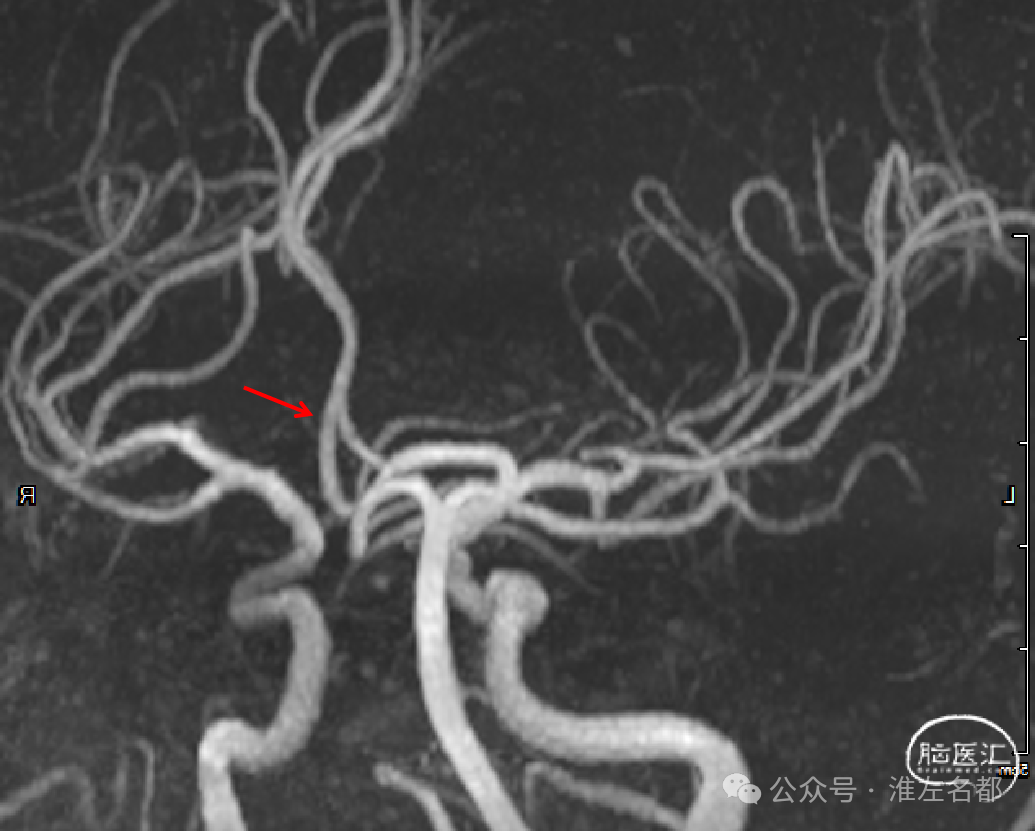

微导管通过闭塞位置,造影证实位于真腔。

经微导管释放取栓支架(S AB 4*20mm)后造影,前向血流恢复,局部狭窄(红箭)。

回收取栓支架后造影:闭塞再通,右侧A2局部轻微狭窄,但A3-4交界处可见造影剂渗出,提示出血。

予以降压等处理,约5分钟后造影提示出血已经停止。

取出少量血栓

术中DSA平板CT示:前纵裂旁少量蛛网膜下腔出血。